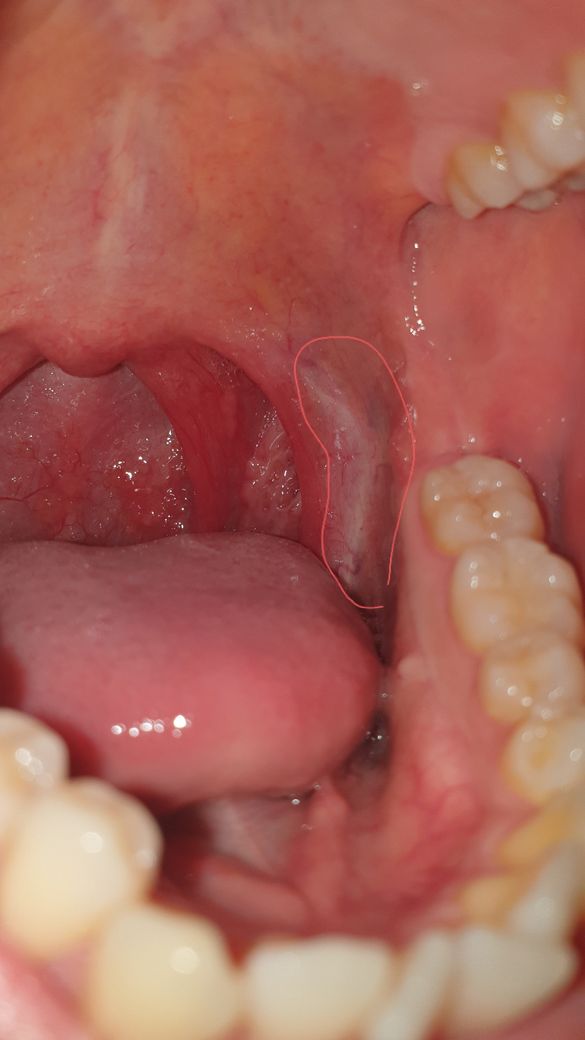

1 2 사진에서처럼 양쪽 막 근처에 살짝 하얗게 되어있고 안쪽으로는 충혈된 것처럼 빨간 느낌입니다

인후부를 사진으로 보았을 때 인후 발적과 함께 왼쪽 편도가 조금 부어 있지만

편도 농양으로 보이지는 않으며 인후통을 동반한 일반적인 감기 증상과 같은 것으로 보입니다.

사진을통하여봤을때는 발적을 동반한 염증이 있어서 목넘김이 힘들고 불편한것으로 생각이됩니다.